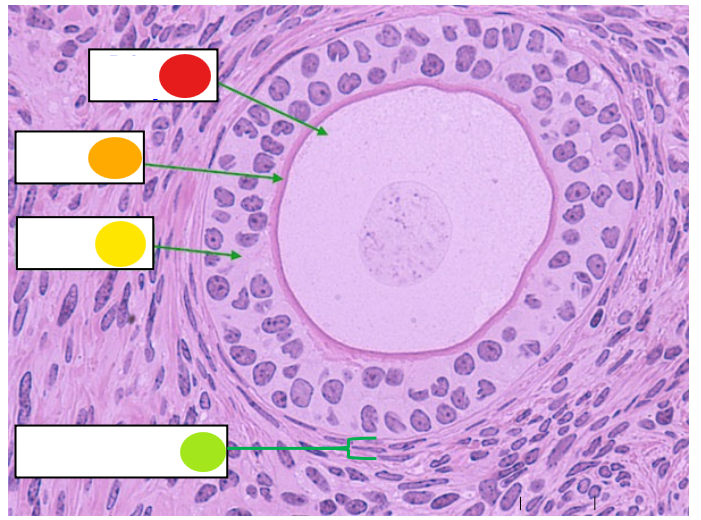

red

primary oocyte

orange

zona pellucida

yellow

granulosa cells

light green

developing thecal cells

What is this

secondary follicle